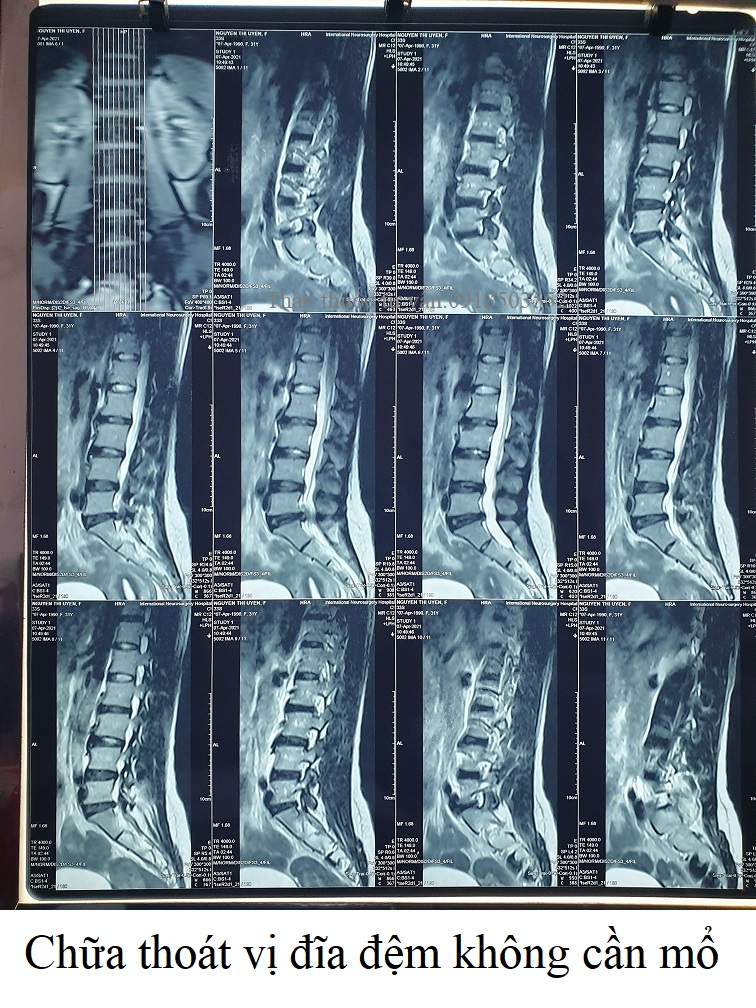

Thoát vị đĩa đệm, rách vòng xơ, chèn rễ L3 trái, chèn rễ L5 phải.Lồi kèm thoát vị đĩa đệm tầng L2-L3, di trú xuống dưới ở ngách bên trái, ép mặt trước bao màng cứng, làm hẹp ngách bên trái, chèn rễ L3 trái. Thoát vị đĩa đệm dạng trung tâm tầng L4-L5, có rách vòng xơ, có mảnh rời di trú xuống dưới ở ngách bên phải, ép mặt trước bao màng cứng, chèn ép rễ L5 phải. Thoái hóa cột sống thắt lưng.❮ đọc tiếp ❯

Thoát vị đĩa đệm dạng trung tâm, có rách vòng xơ.Thoát vị đĩa đệm dạng trung tâm tầng L4-L5, có rách vòng xơ, có mảnh rời di trú xuống dưới ở ngách bên phải, ép mặt trước bao màng cứng, chèn rễ L5 phải. Thoái hóa cột sống thắt lưng.❮ đọc tiếp ❯